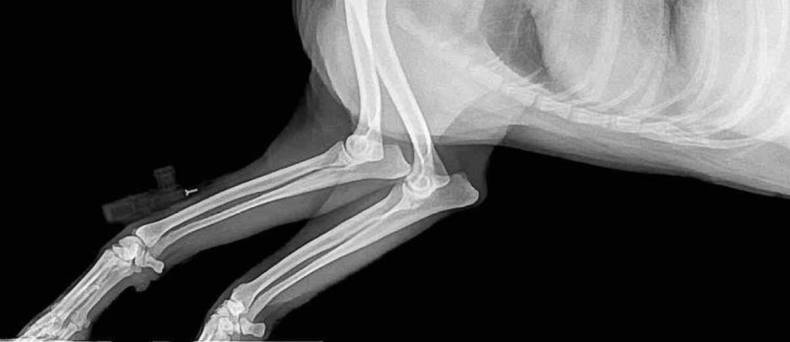

Diagnose van spondylose bij honden kan worden gesteld door middel van een röntgenfoto van de wervelkolom. Aanvullende tests, zoals bloedonderzoek of een MRI, kunnen ook nodig zijn om andere aandoeningen uit te sluiten die vergelijkbare symptomen kunnen veroorzaken.